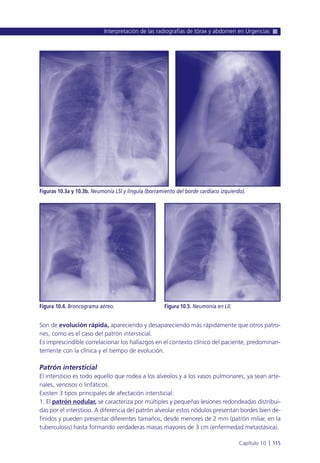

10.-Interpretación de las radiografías de tórax y abdomen en Urgencias ..... 111

P.M. Hernández Guilabert, R. Morcillo Carratalá, P.M. Aguilar Angulo,

M.C. Ruiz Yagüe, A. Julián Jiménez